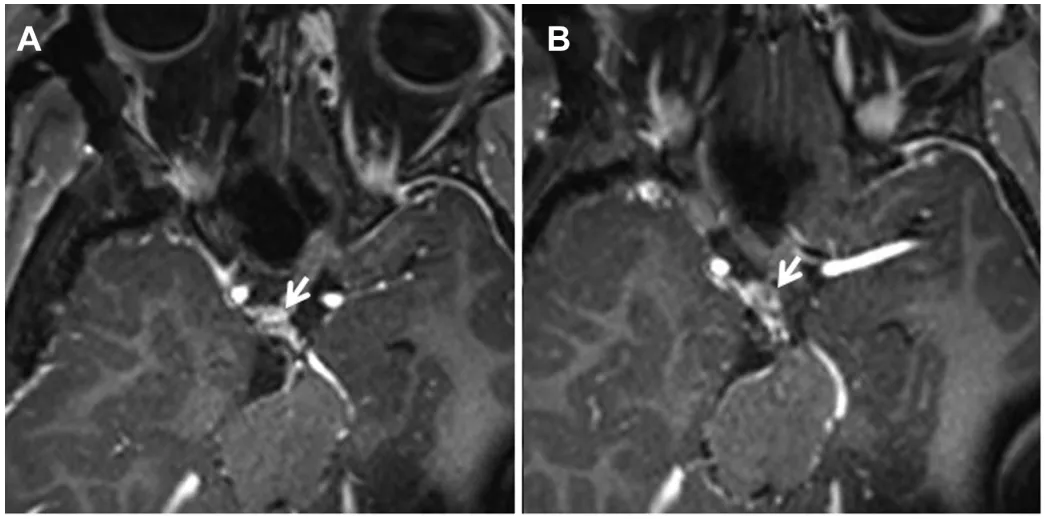

术后动眼神经麻迅速改善,3个月复查功能完全恢复。病理证实为神经鞘瘤(图3A)。

术后MRI